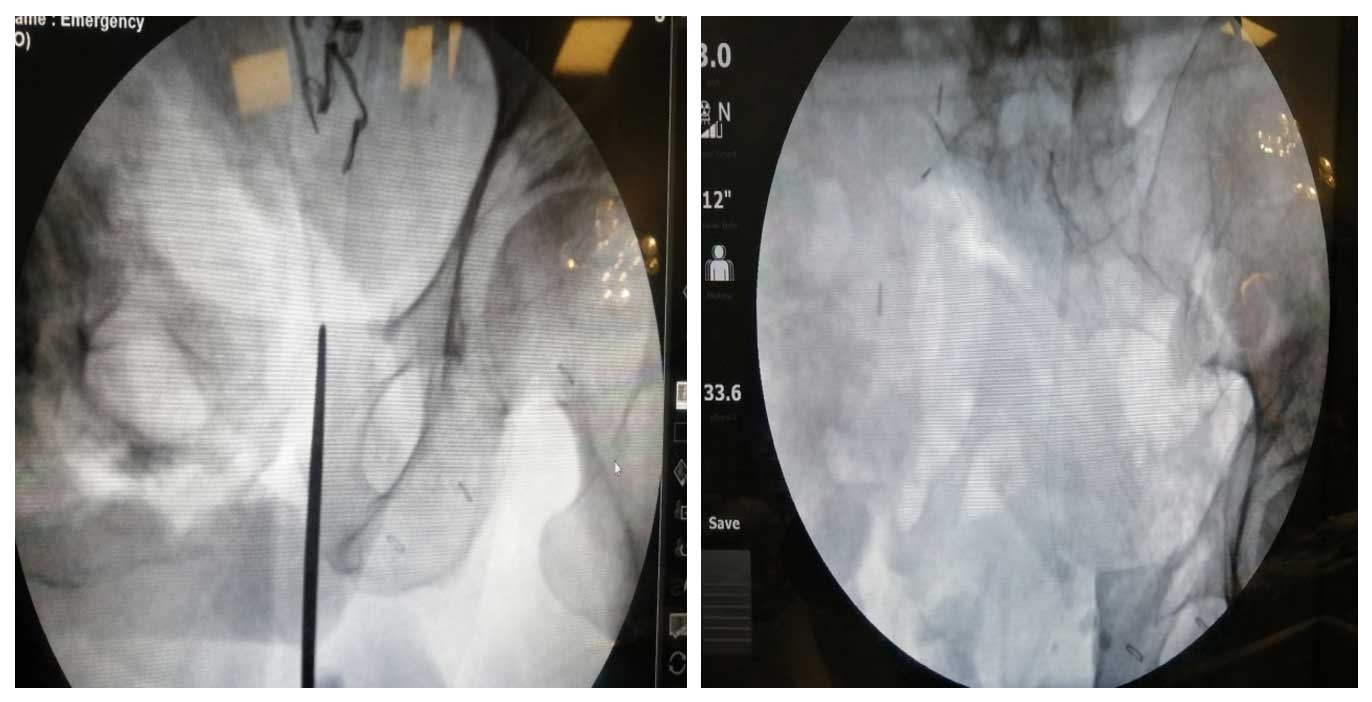

Ameliyat Esnası: Skopide osteotom ile kesim seviyesinin planlanması ve rezeksiyon sonrası görülmekte.